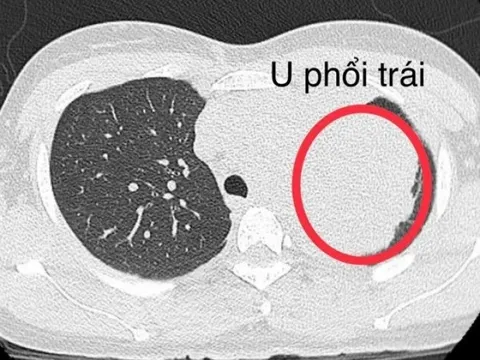

Đi khám vì đau bả vai, người phụ nữ trẻ mắc ung thư phổi

Khai thác tiền sử bản thân và bố mẹ của người phụ nữ không ai mắc ung thư, nhưng chồng bệnh nhân nghiện thuốc lá gần 20 năm nay.